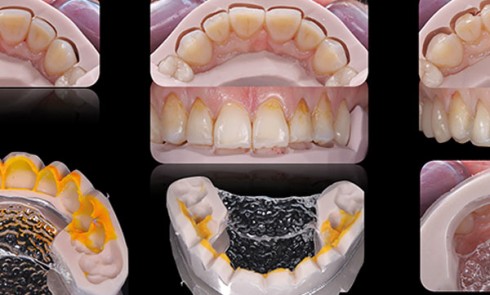

En préambule Avant tout, pour que le contrôle puisse se faire, il est primordial de passer par une phase d’étude...

À l’écran, il est possible de choisir un modèle d’articulateur parmi plusieurs propositions. L’opérateur peut ainsi faire apparaître un articulateur,...

Un patient de 68 ans arrive au cabinet ; il présente de nombreux édentements ainsi qu’une usure parafonctionnelle très avancée.Il consulte...